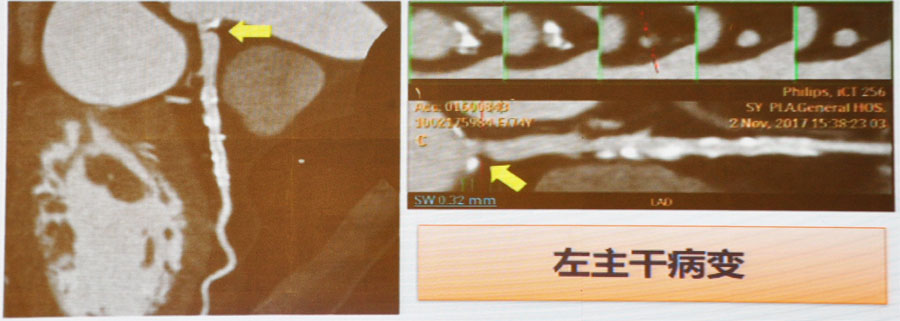

3. 冠脉CT(CTA)

可判断冠脉官腔狭窄程度和管壁钙化情况,有较高的阴性预测价值(99%)。优点是简单、快速、无创;缺点是受心率、钙化等因素限制。

图3 左主干病变